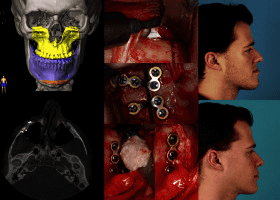

It moves cheekbones upward, give so much under eye support and even change orbital shape. Also widen face and change gonial angle. Is it modified lefort 3?